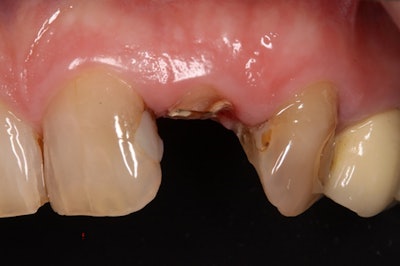

A patient's isogingivally fractured maxillary lateral incisor.Images courtesy of Graf et al. Licensed by CC BY 4.0.

To avoid extractions, several extrusion techniques have been described to restore teeth with insufficient coronal tooth structure. However, there is limited research on the use of an atraumatic axial extraction system combined with surgical extrusion to restore seriously damaged teeth.